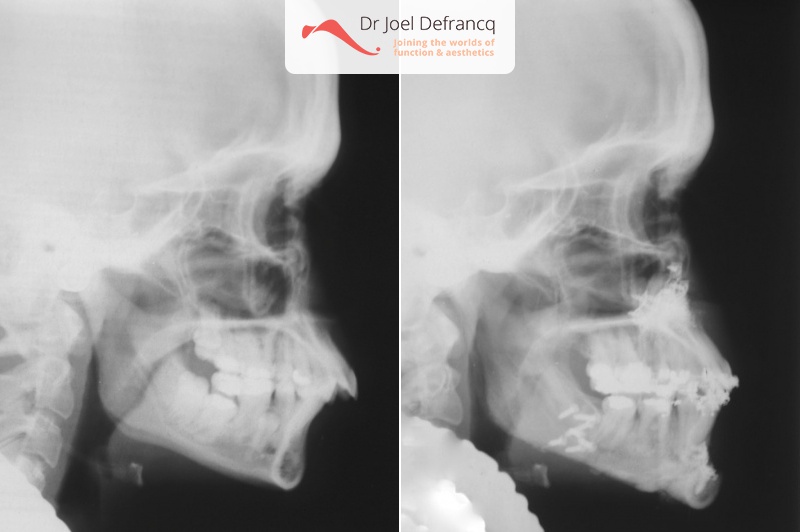

Damisi:upper jaw too far forward, weak chin.

Diagnose van het gezicht

- Te kleine onderkaak (Overbeet)

- Te grote bovenkaak

- Te brede onderkaak

Dentale diagnose

- Klasse II divisie 1

Kaakchirurgie

- Verlenging onderkaak (BSSO)

- Naar achter plaatsen bovenkaak (Le Fort I)

- Kinchirurgie

- Bovenkaak werd tevens versmald via midline split